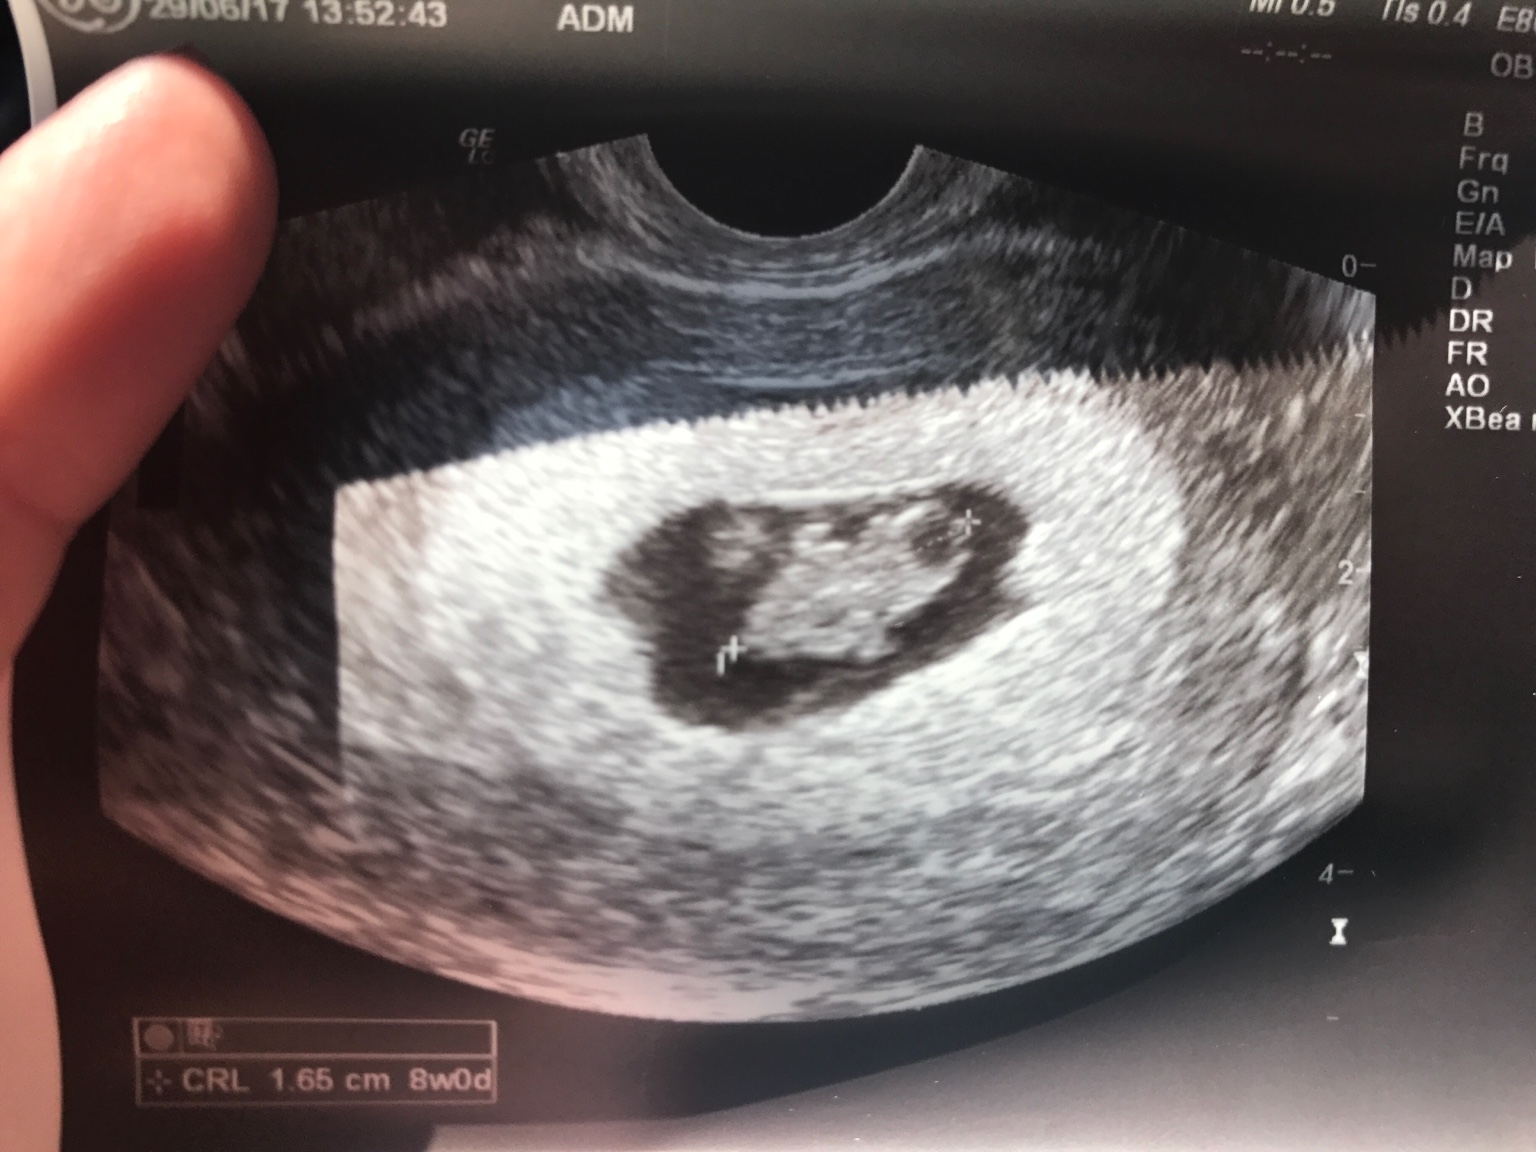

Mój Maluszek coraz bardziej przypomina człowieczka [emoji64]póki co wszystko idealnie [emoji16][emoji16]